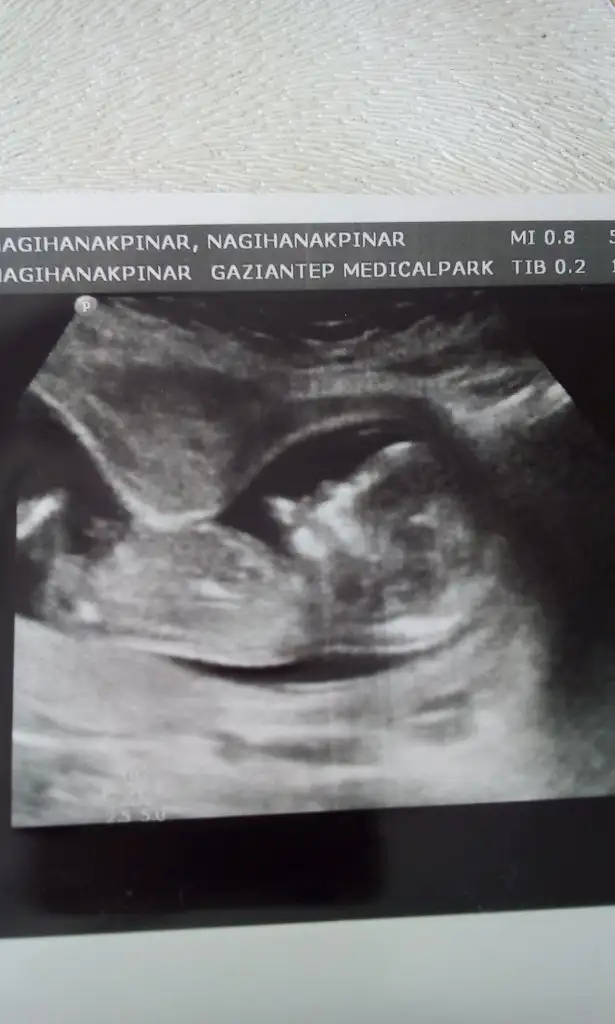

Kızlar benimki bu teoriye göre kız mi oluyor 7 haftalık bu görüntü şuan 11 iz vajinal ultrason buda.

Eklentiler

• 20200429_211853.webp

20200429_211853.webp

27,8 KB · Görüntüleme: 164